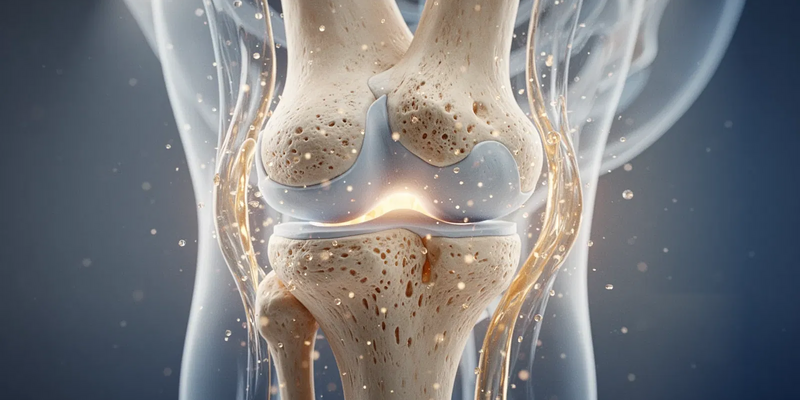

Lange hieß es: Schonen bei Arthrose. Heute ist das Gegenteil wissenschaftlich belegt. Der Gelenkknorpel ernährt sich über die Gelenkflüssigkeit, die nur bei Bewegung produziert und verteilt wird. Dieser „Schwammeffekt“ hält das Gewebe geschmeidig. Bewegungsmangel unterbricht die Nährstoffversorgung und beschleunigt den Abbau.

Zudem wirkt eine kräftige Muskulatur wie ein natürlicher Stoßdämpfer. Sie stabilisiert Hüfte und Knie, fängt Belastungen ab und entlastet so den Knorpel direkt. Studien zeigen: Bewegungstherapie reduziert nicht nur Schmerzen, sondern kann auch Entzündungen hemmen und den Krankheitsverlauf bremsen.